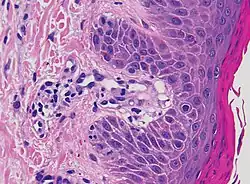

| Lichen planus | Irregular epidermal hyperplasia with a jagged “sawtooth” appearance, compact hyperkeratosis or orthokeratosis, foci of wedge-shaped hypergranulosis, basilar vacuolar degeneration, slight spongiosis in the spinous layer, and squamatization. The dermal papillae between the elongated rete ridges are frequently dome shaped. Necrotic keratinocytes can be observed in the basal layer of the epidermis and at the dermal-epidermal junction. Eosinophilic remnants of anucleate apoptotic basal cells may also be found in the dermis and are referred to as “colloid or civatte bodies”. Whickham striae are usually seen in the areas of hypergranulosis. Vacuolar degeneration at the basal layer may be noted leading to focal subepidermal clefts (Max Joseph spaces). Squamatization occurs as a result of maturation and flattening of cells in the basal layer. It happens in areas of marked hypergranulosis with prominence of the sawtooth pattern of rete ridges. Wedge-shaped hypergranulosis can occur in the eccrine ducts (acrosyringia) or hair follicles (acrotrichia). In the hypertrophic subtype, the associated hyperkeratosis, parakeratosis, hypergranulosis, papillomatosis, acanthosis, and hyperplasia markedly increased with thicker collagen bundles forming in the dermis. Moreover, the rete ridges are more elongated and rounded as opposed to the typical sawtooth pattern. In atrophic LP, loss of the rete ridges and dermal fibrosis is prominent. In vesiculobullous LP, the disease progression is quicker. Hence, some of the distinctive features such as hyperkeratosis, hypergranulosis, or dense lymphocytic dermal-epidermal infiltrate may not be present. LP lesion may resolve with residual hyperpigmentation caused by a persistent increase in the number of melanophages in the papillary dermis.[9] | ![]() |

|